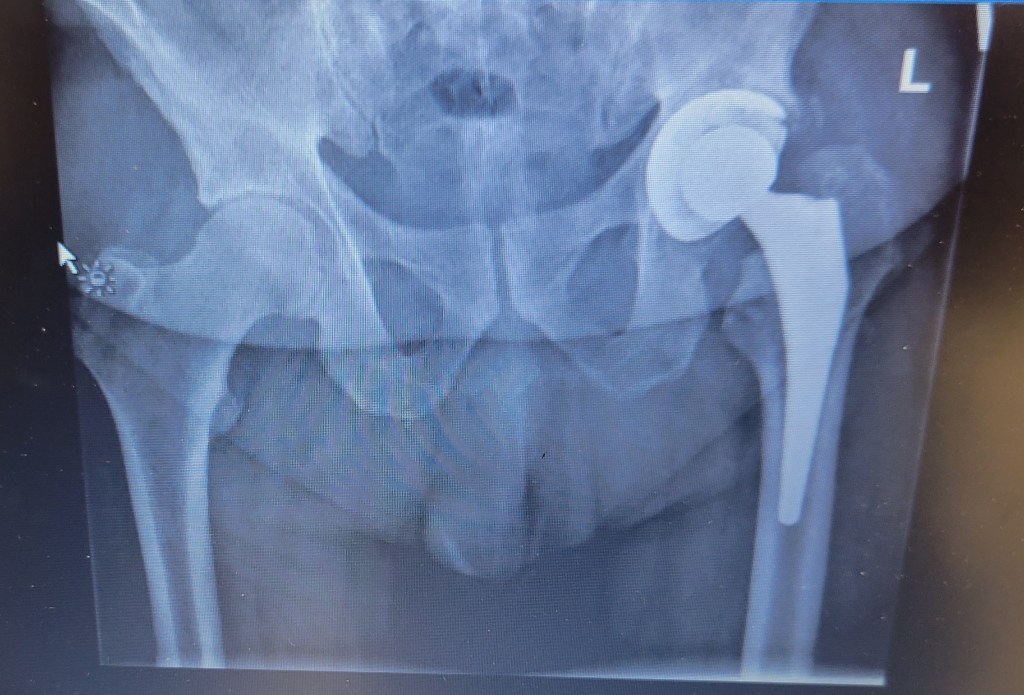

Thought I’d wrap up with an xray of my new hip. I thought it was pretty cool. The main part is titanium. Does that make me the Bionic Man?